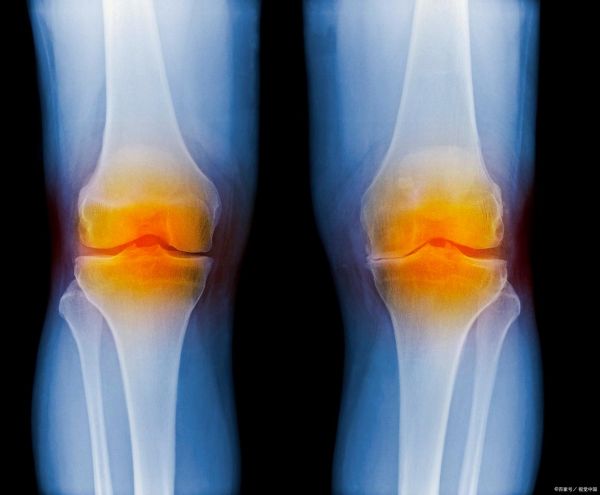

中南大學(xué)湘雅醫(yī)院研究團隊在《風(fēng)濕病年鑒》發(fā)表的研究顯示,每天大約8000步,對預(yù)防膝關(guān)節(jié)疾病最為理想,這個強度和數(shù)量,可以增強肌肉力量、改善關(guān)節(jié)穩(wěn)定性、減輕關(guān)節(jié)負擔(dān)。超過8000步時,對關(guān)節(jié)的益處不會再增加。

中老年人、運動員或有膝蓋損傷史的人群,建議每年進行一次X光、磁共振成像等檢查,以便在問題剛出現(xiàn)時就能采取有效治療措施,防止病情惡化。